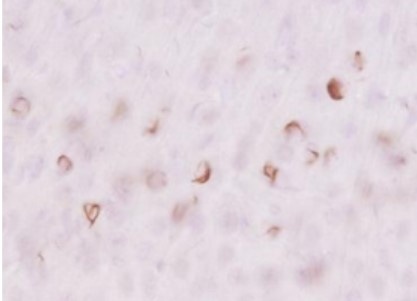

Immunohistochemistry

+

Biotin-conjugated secondary antibody

Species: Mouse (6 months old, wild-type, injected intracerebrally with aggregated α-synuclein)

Site: Striate

Sample: Vibratome section (50 μm thick)

Antibody concentration: 1:1,000

Staining: DAB staining

Data by courtesy of

Drs. Kuwahara and Iwatsubo, Graduate School of Medicine, The University of Tokyo

[Result]

By combining the biotin-labeled antibody with the ABC method, background staining was reduced compared with detection using a secondary antibody, resulting in clearer, more distinct staining.